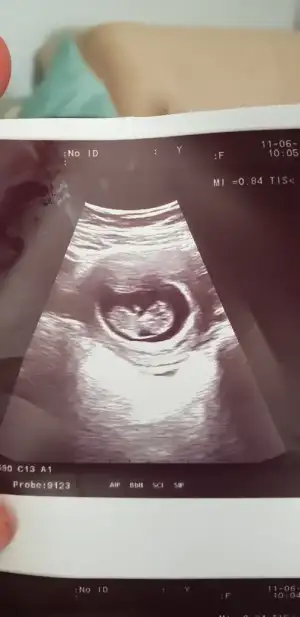

Merhaba.. benim icin de bir tahmin yaparmisiniz?

6+3 usg karindan